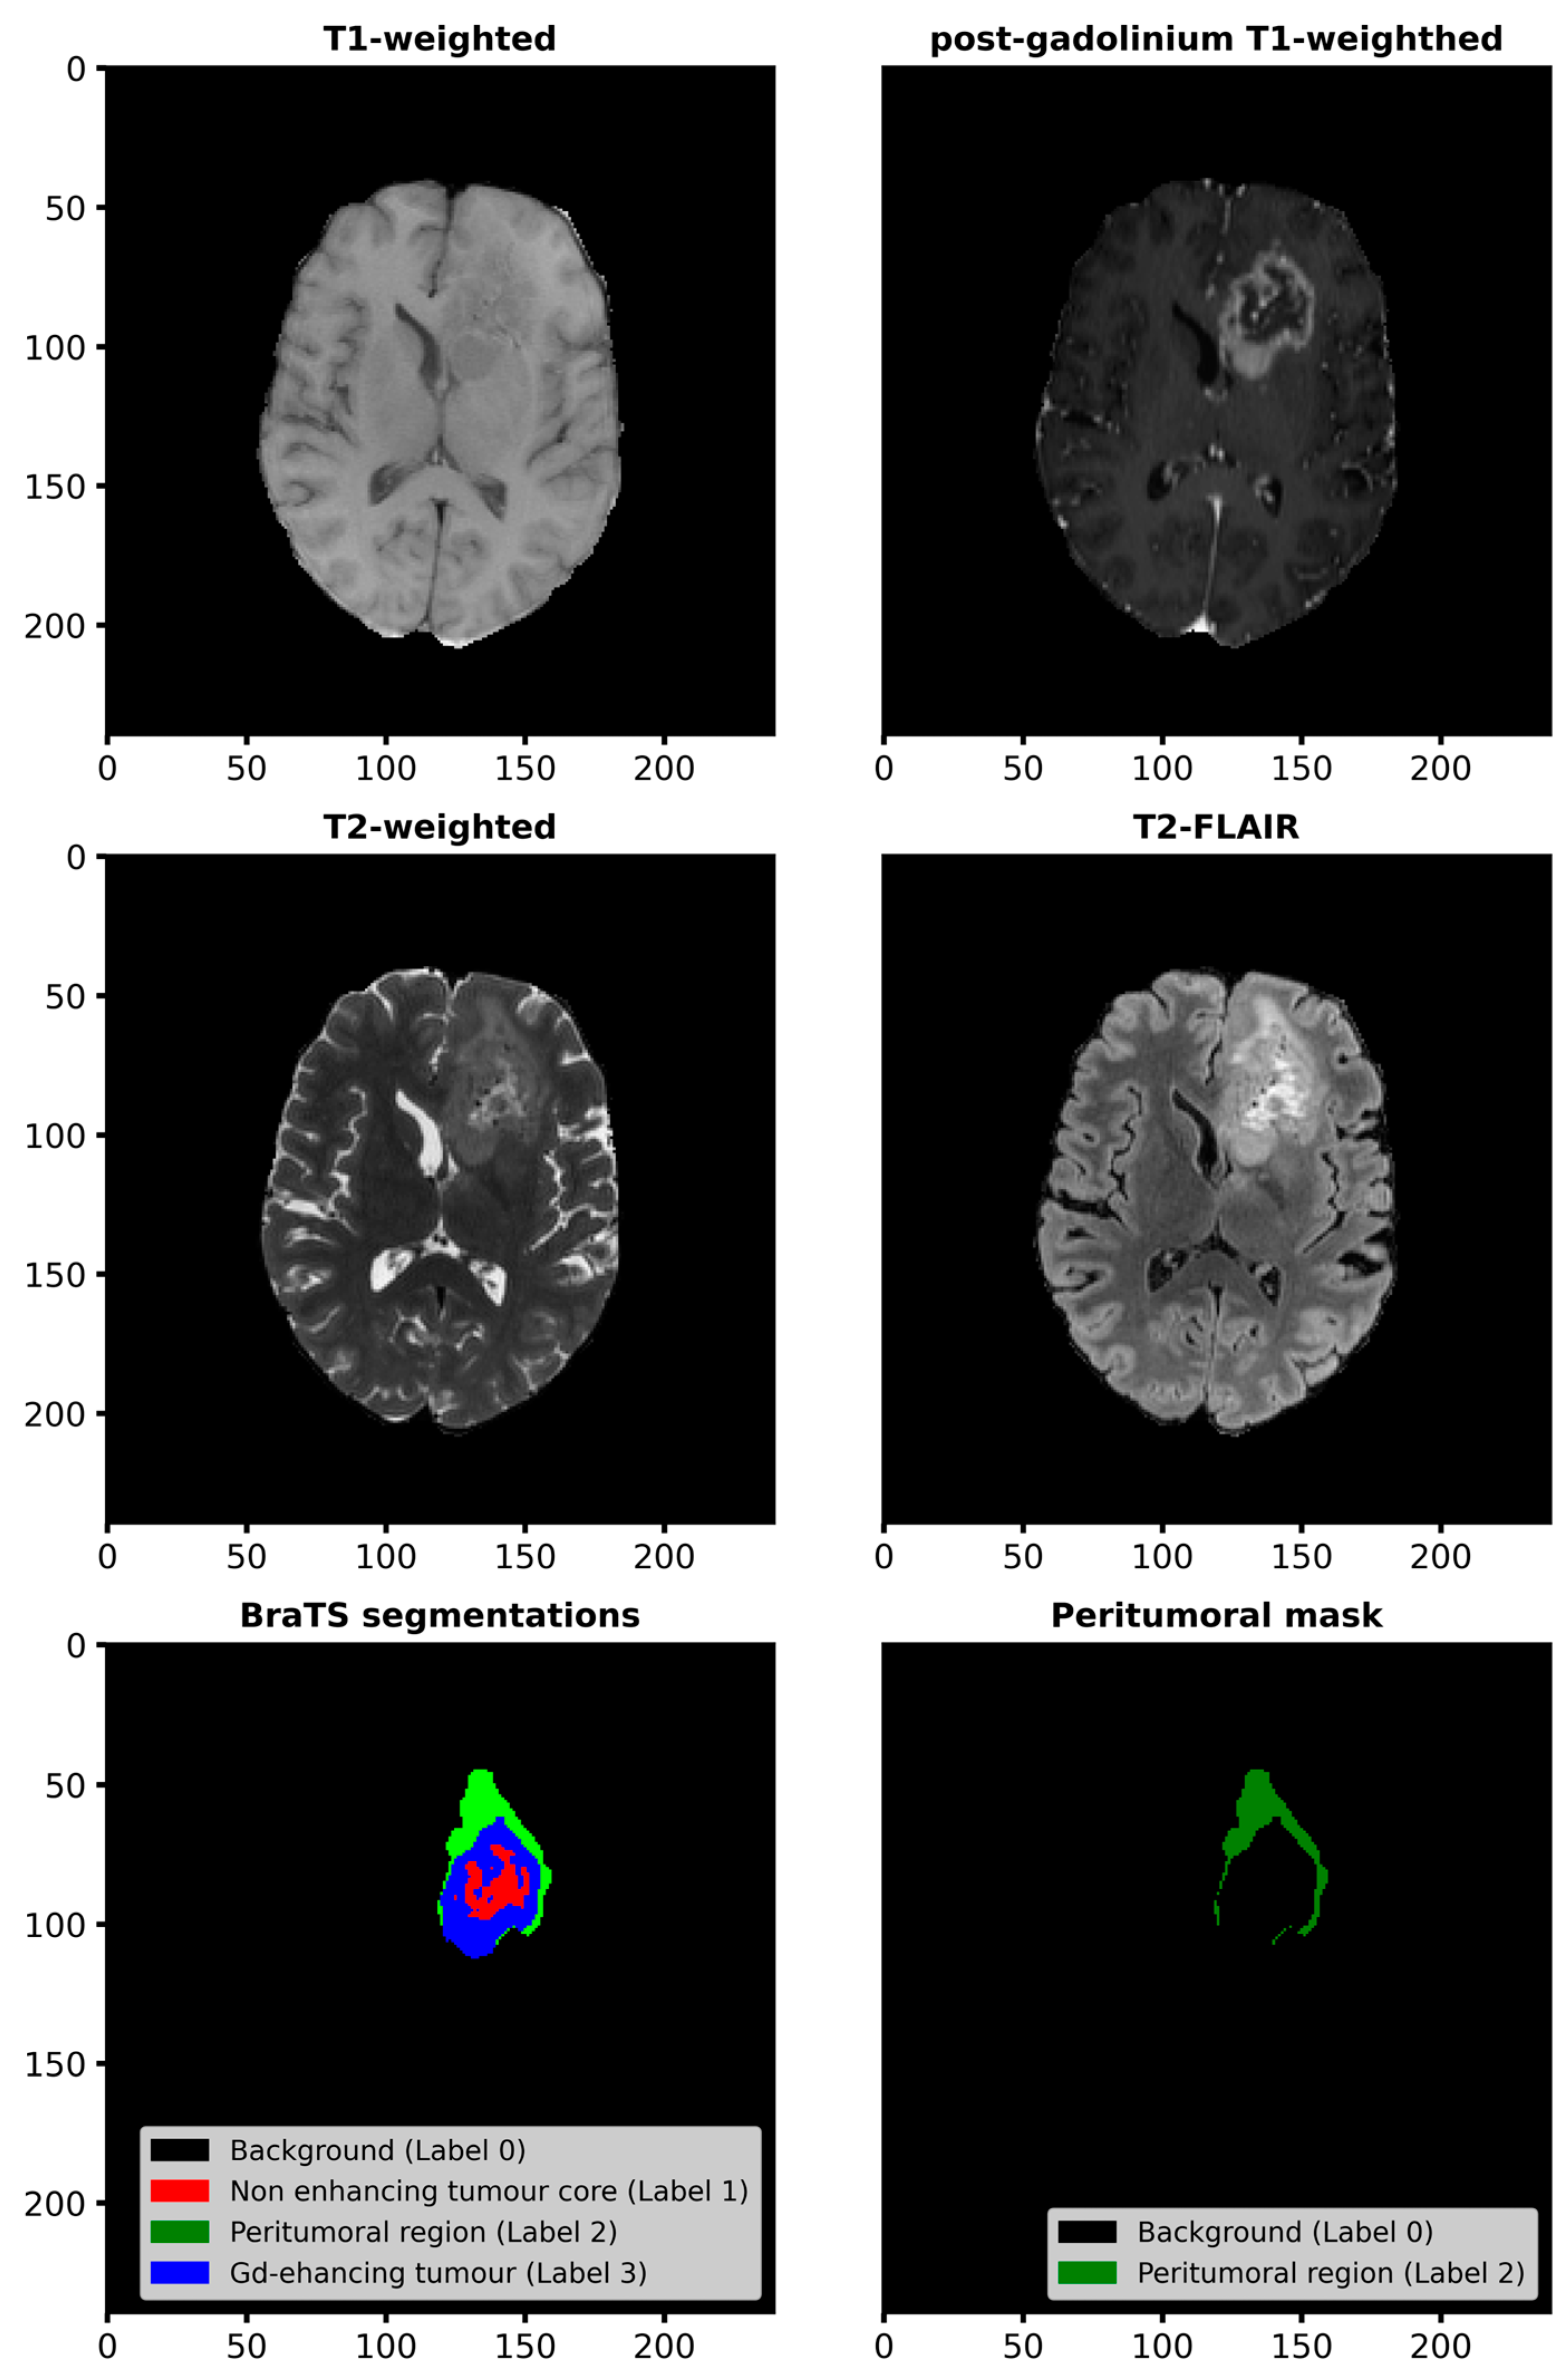

2.2.1. Workflow for Radiomic Feature Extraction and Tumor Classification

2.2.2. Radiomic Feature Extraction